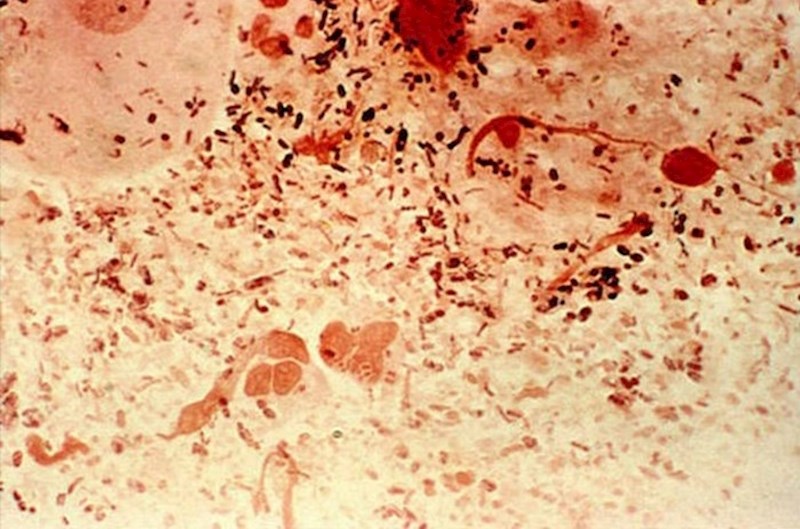

Mikrobiolozi Sveučilišta u Idahou (SAD) tvrde da je broj bakterijskih stanica koje žive u našim tijelima 10 puta veći od broja naših vlastitih stanica, no to nije loša stvar jer većinu tih bakterija trebamo. Drugim riječima, riječ je o dobrim bakterijama.

Najjača stvorenja na Zemlji zapravo su bakterije, točnije uzročnici gonoreje. Mogu vući masu 100 tisuća puta veću od vlastite mase.